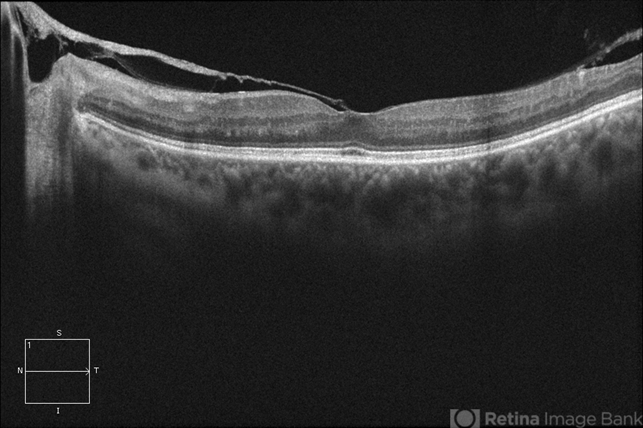

- vitreomacular traction (VMT), 20/25, optical coherence tomography (OCT)

Optical coherence tomography system

Cirrus - Description

- OCT of an 56-year-old woman with diabetic retinopathy, VA 20/25.